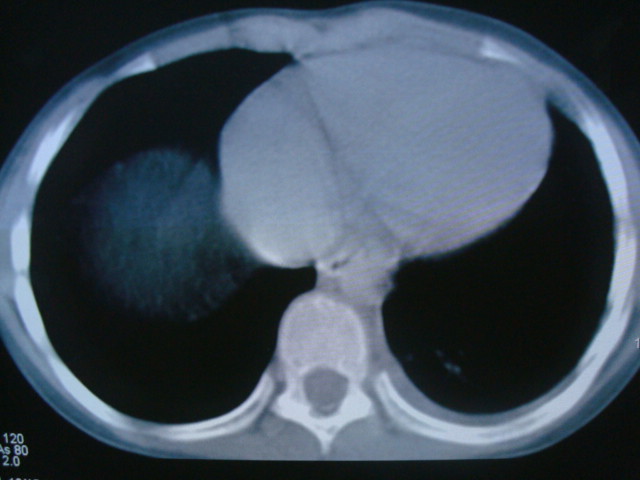

标题: PED0869:男,10岁,肺内多发结节+胸水 [打印本页]

标题: PED0869:男,10岁,肺内多发结节+胸水

男,10岁,左胸痛,发热轻,血象高。后到省级权威医院治疗,病情明显好转,结果几天后公布。老机器,图像质量差,见谅。

考虑血源性肺脓肿或韦氏肉芽肿

考虑血源性肺脓肿

考虑化脓性肺炎。